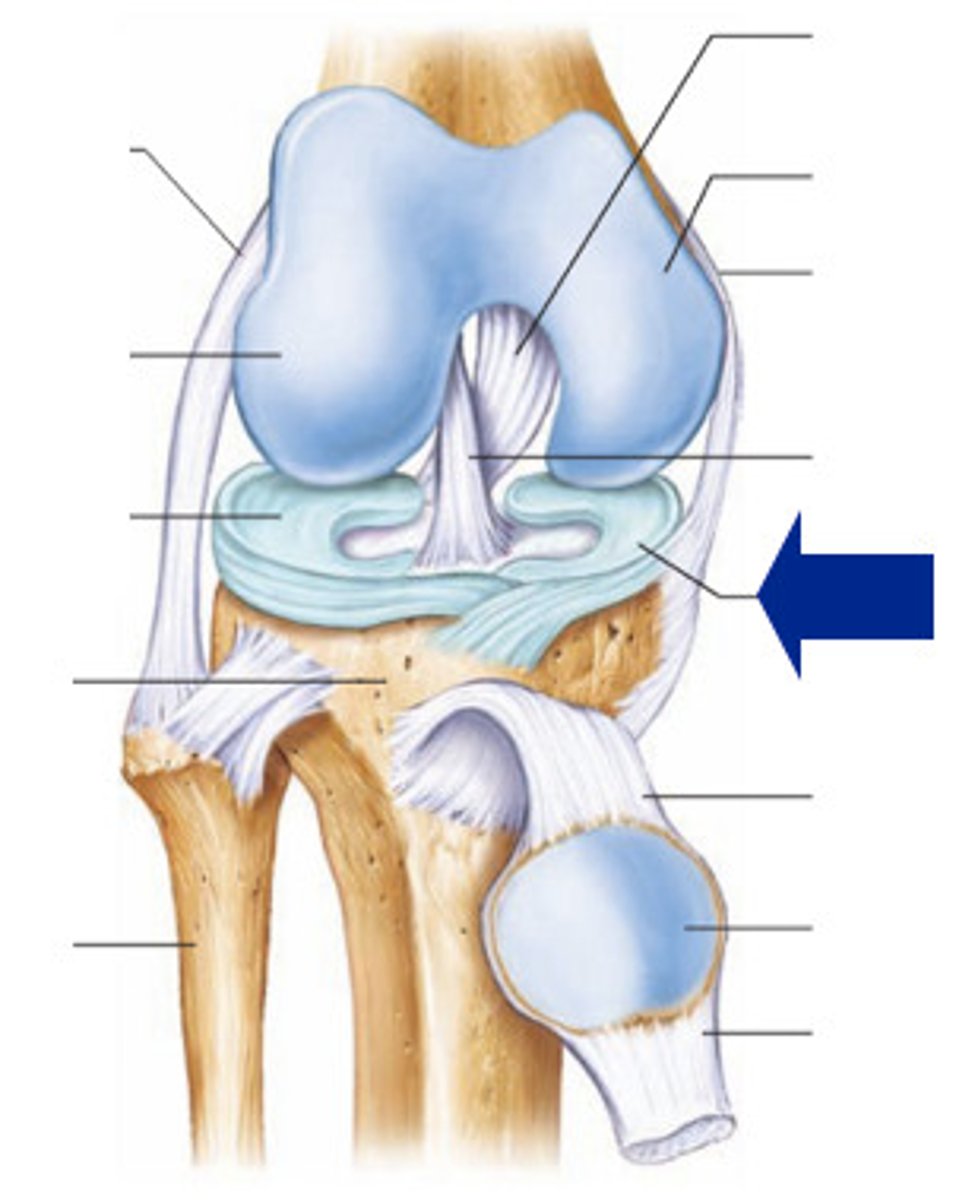

Medial meniscus

Lateral meniscus

Anterior cruciate ligament

Posterior cruciate ligament

Medial (tibial) collateral ligament

Lateral (fibular) collateral ligament